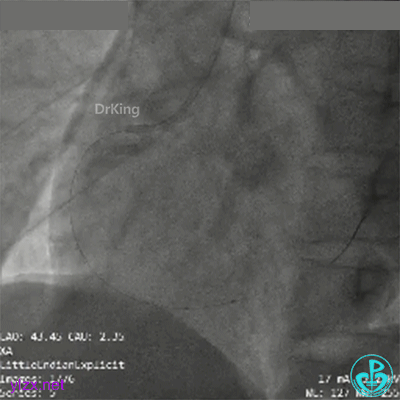

超声证实PL延伸至近端血肿,近端可见夹层破口。

近端3.5×33mm支架至开口,中段接3.0×33mm支架。后扩张处理后远端仍然造影剂滞留。

PL近端2.5mm切割球囊扩张后,造影剂滞留改善。

远端至PL近端接2.75×33mm支架后,血流彻底恢复。

3.0×15mm及3.5×15mm球囊优化以后最后造影。

超声证实支架膨胀及贴壁良好,血肿消失,症状缓解。好惊险!